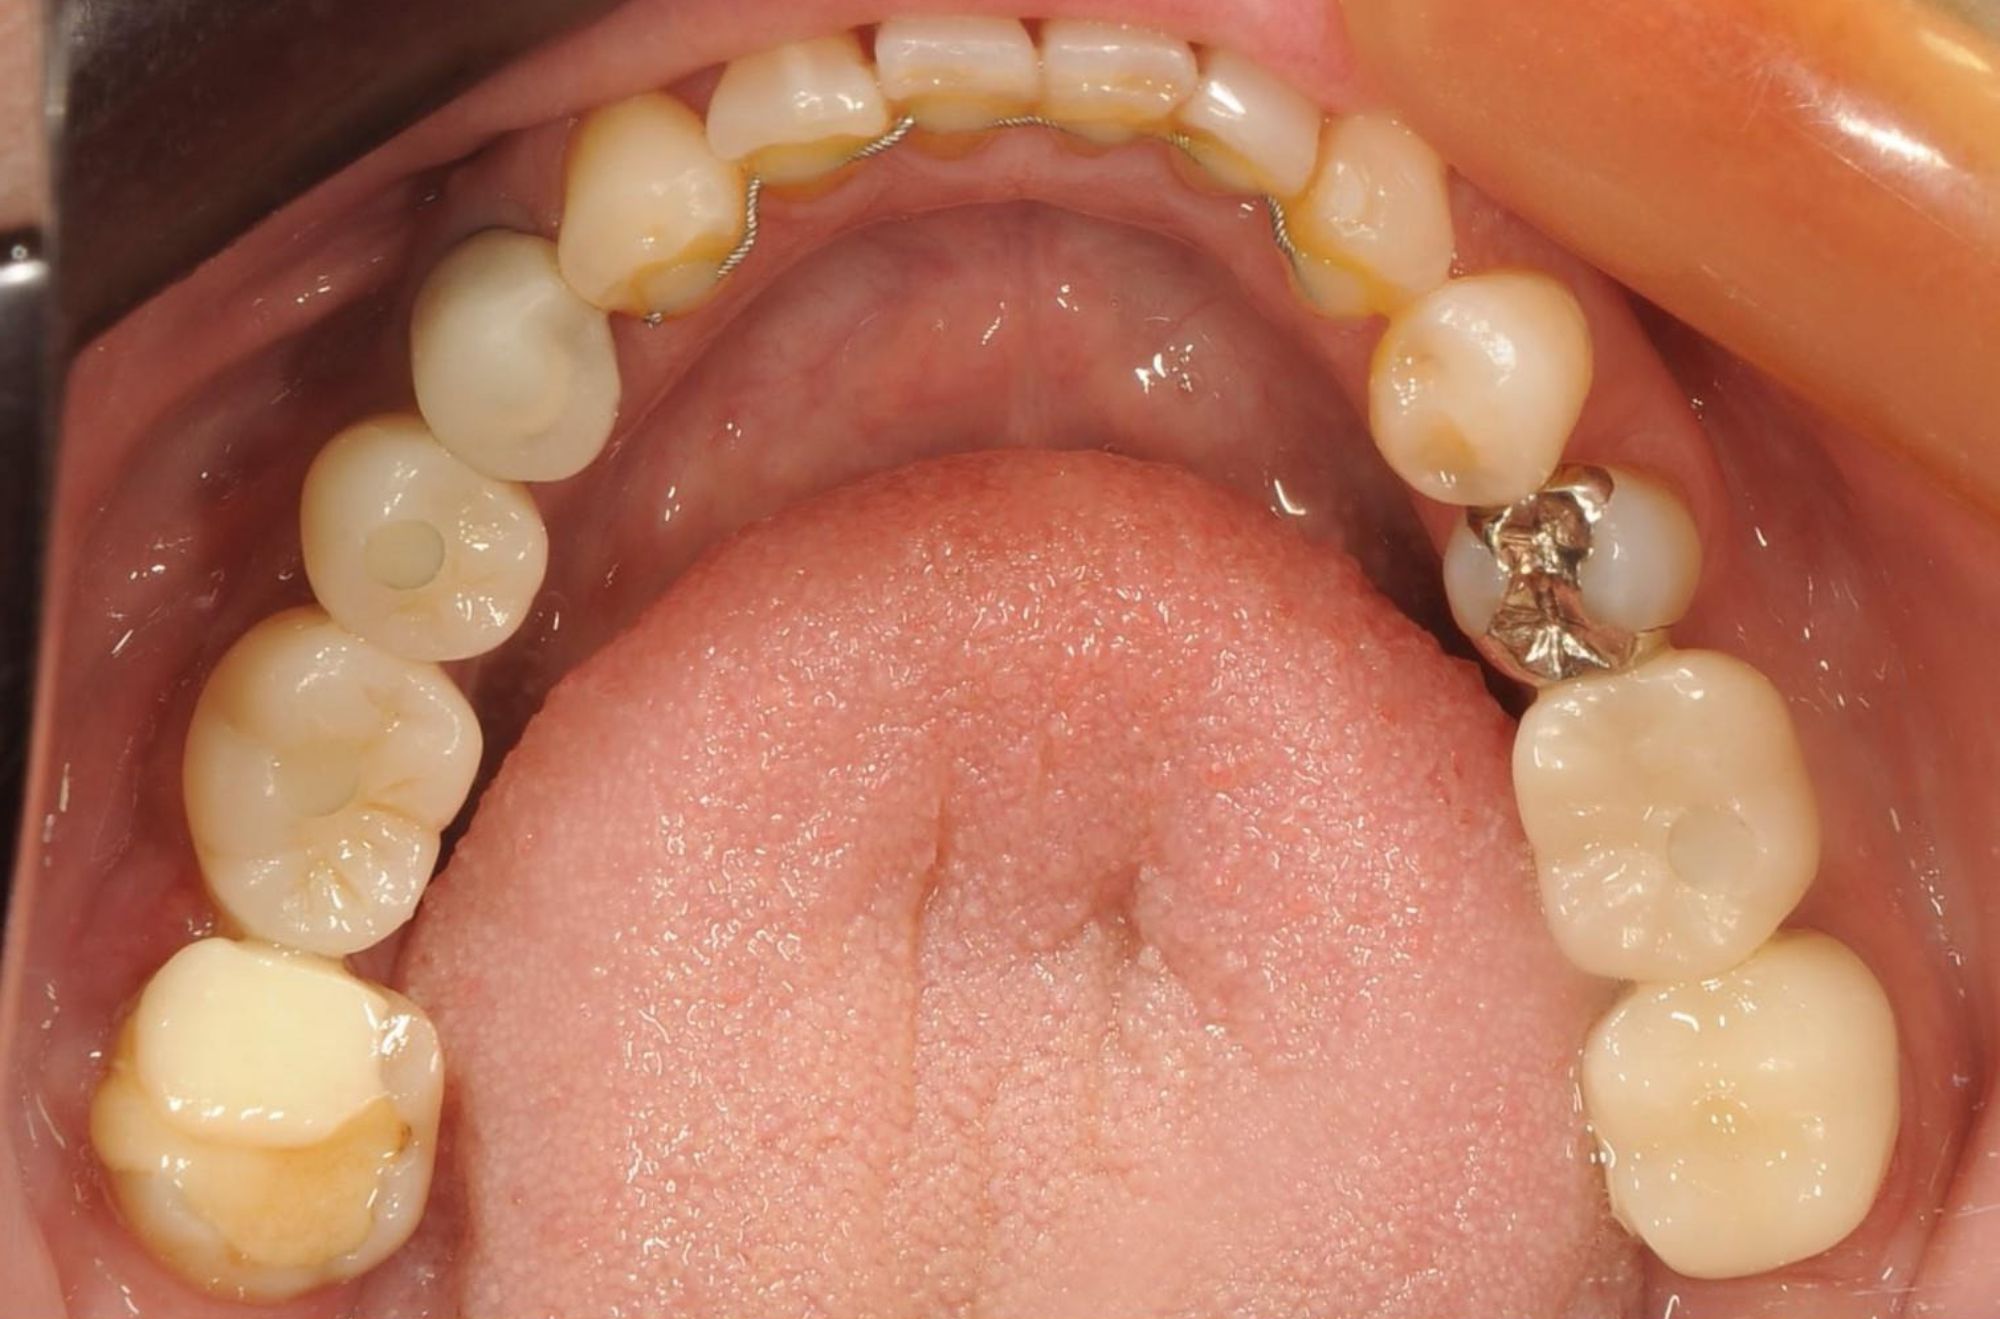

case.02

差し歯とインプラントの治療

若年の患者様が前歯の審美性について相談に来られました。差し歯とインプラントの組み合わせにより、自然で美しい笑顔を実現しました。患者様は見た目の改善と機能性の向上に大変満足されました。